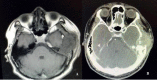

Figure 2.. Radiological scan A) MRI temporal–axial view T1 weighted B) CT scan temporal–axial view. Soft tissue tumor over the left temporal region causing compression of the temporal lobe and local bony erosion.